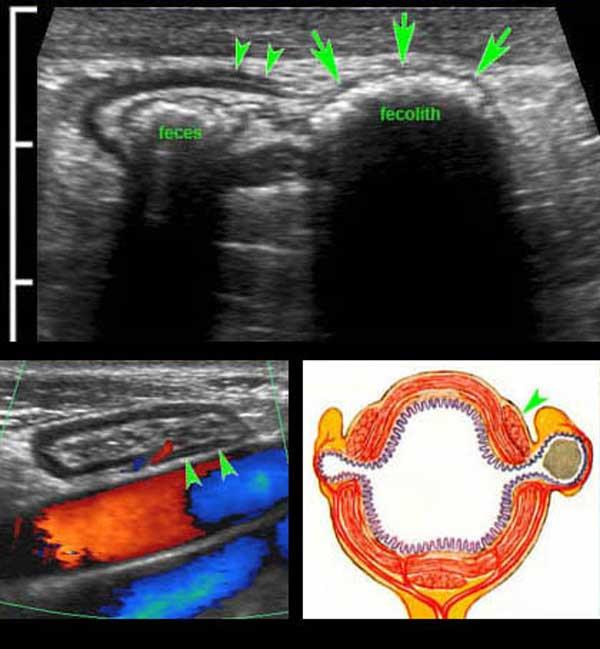

Hình ảnh siêu âm chi tiết của túi thừa đại tràng sigma ở bệnh nhân 61 tuổi rất gầy.

Có một ít phân trong lòng đại tràng sigma và một sỏi phân lớn trong túi thừa (mũi tên).

Lưu ý thành túi thừa rất mỏng, bao gồm lớp (dưới)niêm mạc thoát vị được bao phủ bởi một lớp thanh mạc rất mỏng.

Sự thoát vị qua lớp cơ, luôn luôn xảy ra tại điểm yếu nơi các mạch máu xuyên qua lớp cơ vòng, ngay cạnh dải cơ dọc kết tràng (mũi tên). Các mạch máu xuyên này được xác định bằng Doppler màu ở một bệnh nhân rất gầy khác (dưới bên trái) và được minh họa trong hình ảnh Netter ở dưới bên phải.